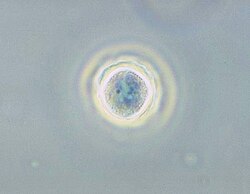

Acanthamoeba es un género de Amoebozoa, uno de los protistas más comunes del suelo y también frecuentes en agua dulce y otros hábitats. Las células son pequeñas, usualmente de 15 a 35 μm de longitud y de forma oval o triangular cuando se mueven. Los seudópodos forman un claro lóbulo semiesférico en la parte anterior y tiene varias extensiones filosas cortas a los lados del cuerpo. Esto le da una apariencia espinosa, a la cual se refiere el nombre Acanthamoeba. Los quistes son comunes y las distintas especies de Acanthamoeba se distinguen principalmente por la forma de los quistes. Muchas especies son amebas de vida libre, pero algunas son oportunistas que pueden causar infecciones en seres humanos y otros animales.